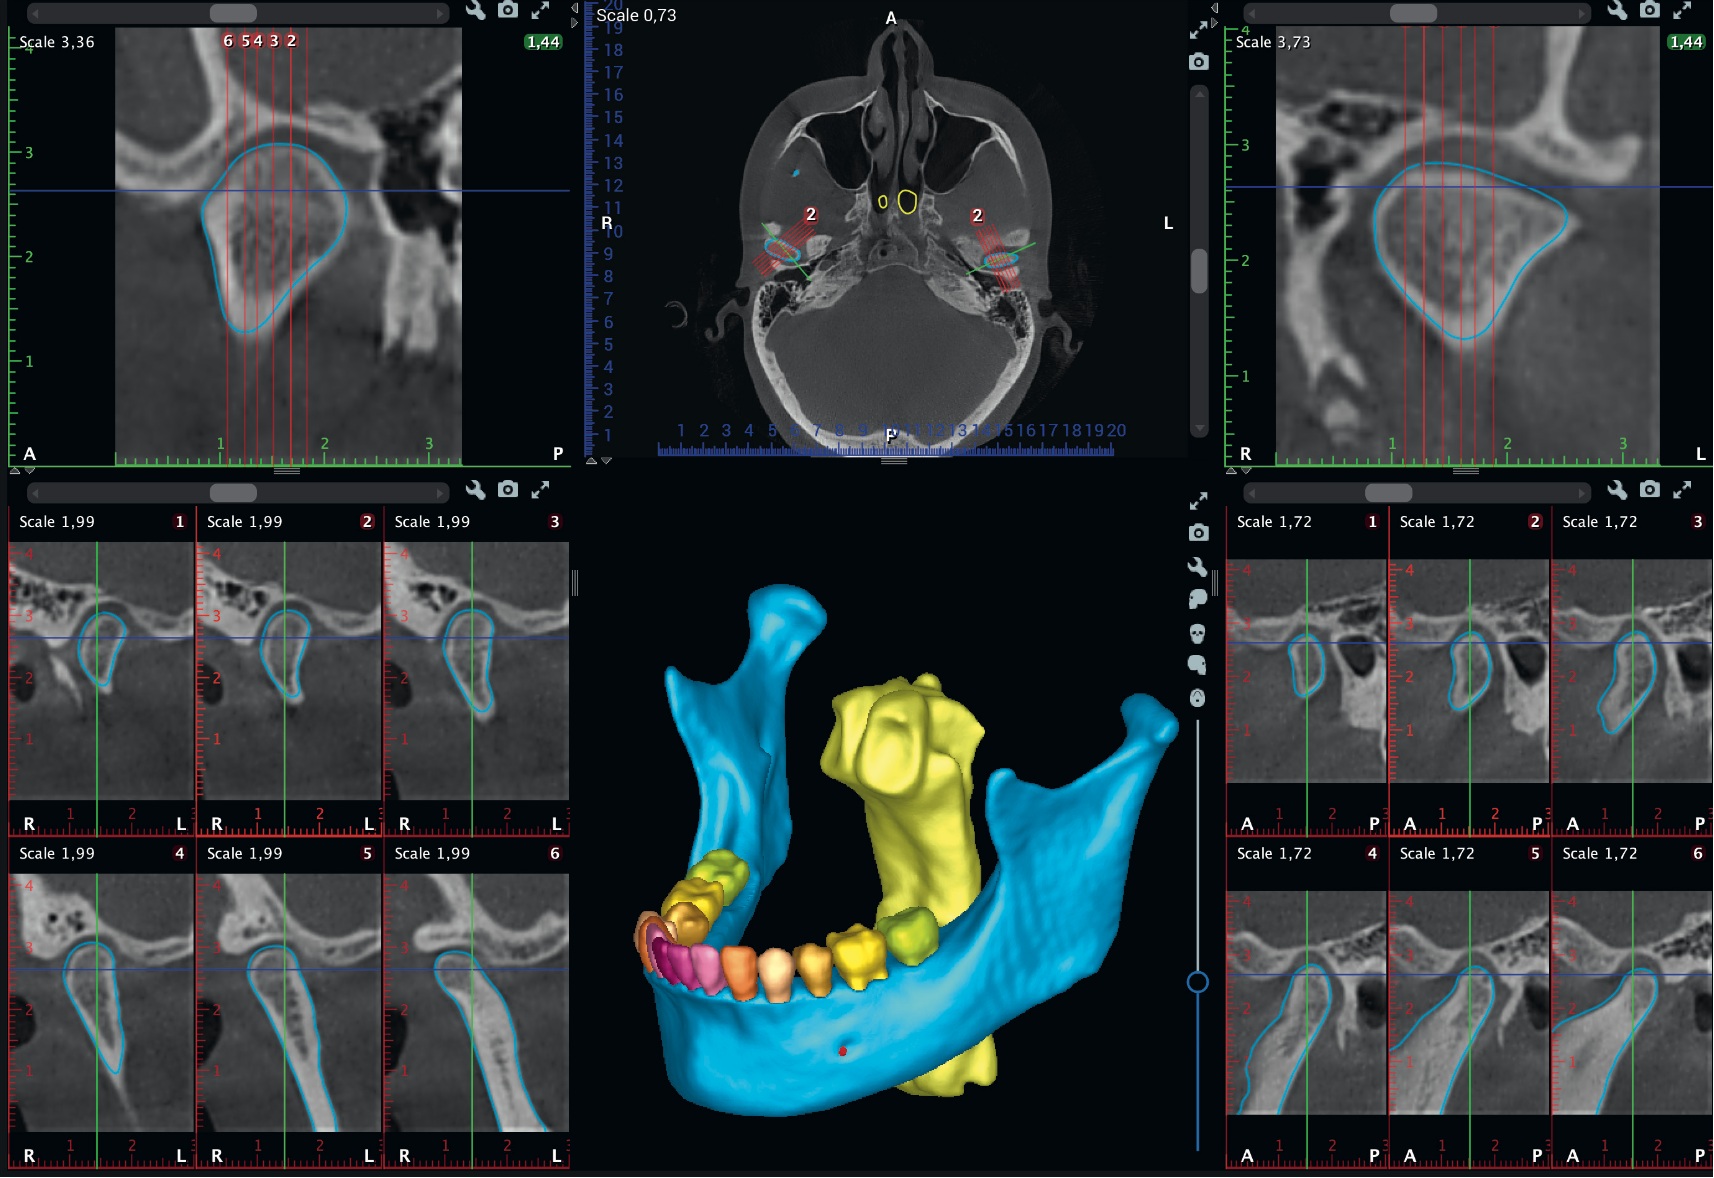

Zobrazení čelistního kloubu (TMJ) - Bolesti temporomandibulárního kloubu (TMJ) postihují významnou část populace. Software Romexis nabízí speciálně navržené náhledy pro vyšetření a analýzu problémů s tímto kloubem. Oba klouby pacienta lze v softwaru vyhodnotit současně a provádět přesná měření. Díky umělé inteligenci Romexis automaticky rozpozná kondyly.

Modul pro 3D zobrazování v softwaru Romexis lze plynule rozšířit na komplexní software pro plánování ošetření, který podporuje plánování implantátů i ortognátní chirurgie. Kompletní implantologický pracovní postup navíc umožňuje navrhovat chirurgické šablony pro zavádění implantátů a dlahy pro ortognátní operace.